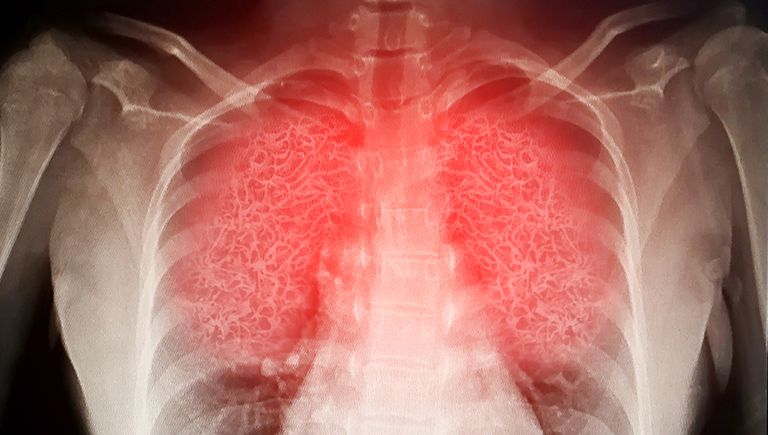

مفاجأة.. الرئة تحتفظ بذاكرة طويلة لعدوى كورونا

رغم أن العديد من الدراسات التي فحصت الدم لتتبع الاستجابات المناعية لفيروس كورونا، لكن أظهرت دراسة جديدة للمتعافين من الفيروس، أن ذاكرة العدوى مخزنة بشكل أساسي في الخلايا التائية والبائية داخل الرئة والعقد الليمفاوية المحيطة بها.